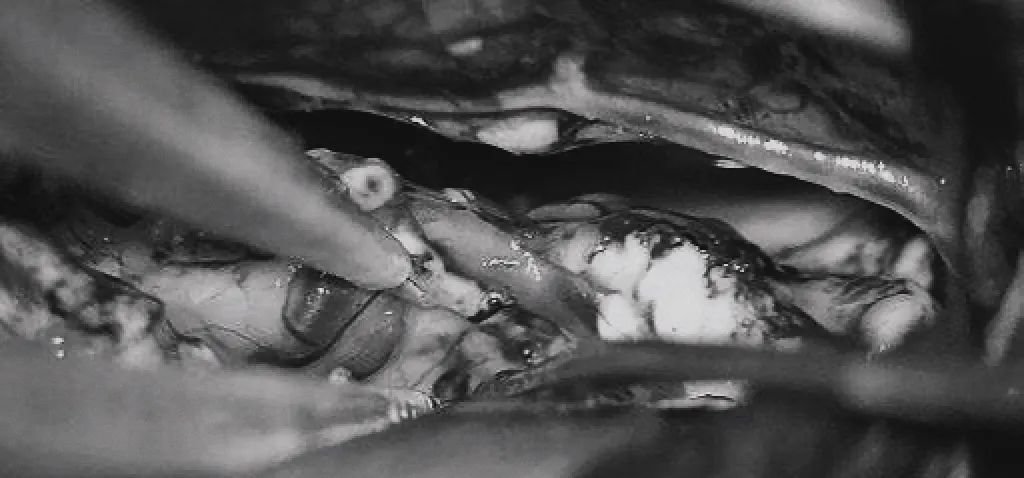

▼右侧眶颧开颅,经侧裂入路,牵开颞极暴露来自ICA鞍上段、MCA的M1段、PCA的P2段和小脑幕切迹。

▼电凝供应颞叶内侧面型AVM的PCA的P2供血支,减少畸形团血供。